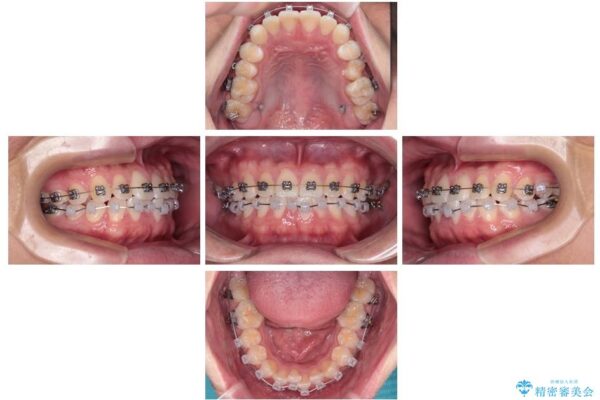

治療途中

• 前歯のガタガタ・奥歯のかみ合わせ(シザーズバイト)を改善|1年半で完了したメタルブラケット矯正 治療途中画像

・上顎左右の第二大臼歯が頬側へ転移し、シザーズバイト(scissors bite)の状態

・上顎左側第二小臼歯が90度捻転しており、噛み合わせに影響

・奥歯のシザーズバイト改善には、口蓋側にアンカースクリュー(TAD)を設置し、矯正用ゴムで内側に牽引

・捻転した第二小臼歯は、ワイヤーと矯正用ゴムの力を用いて正しい位置へ回転移動